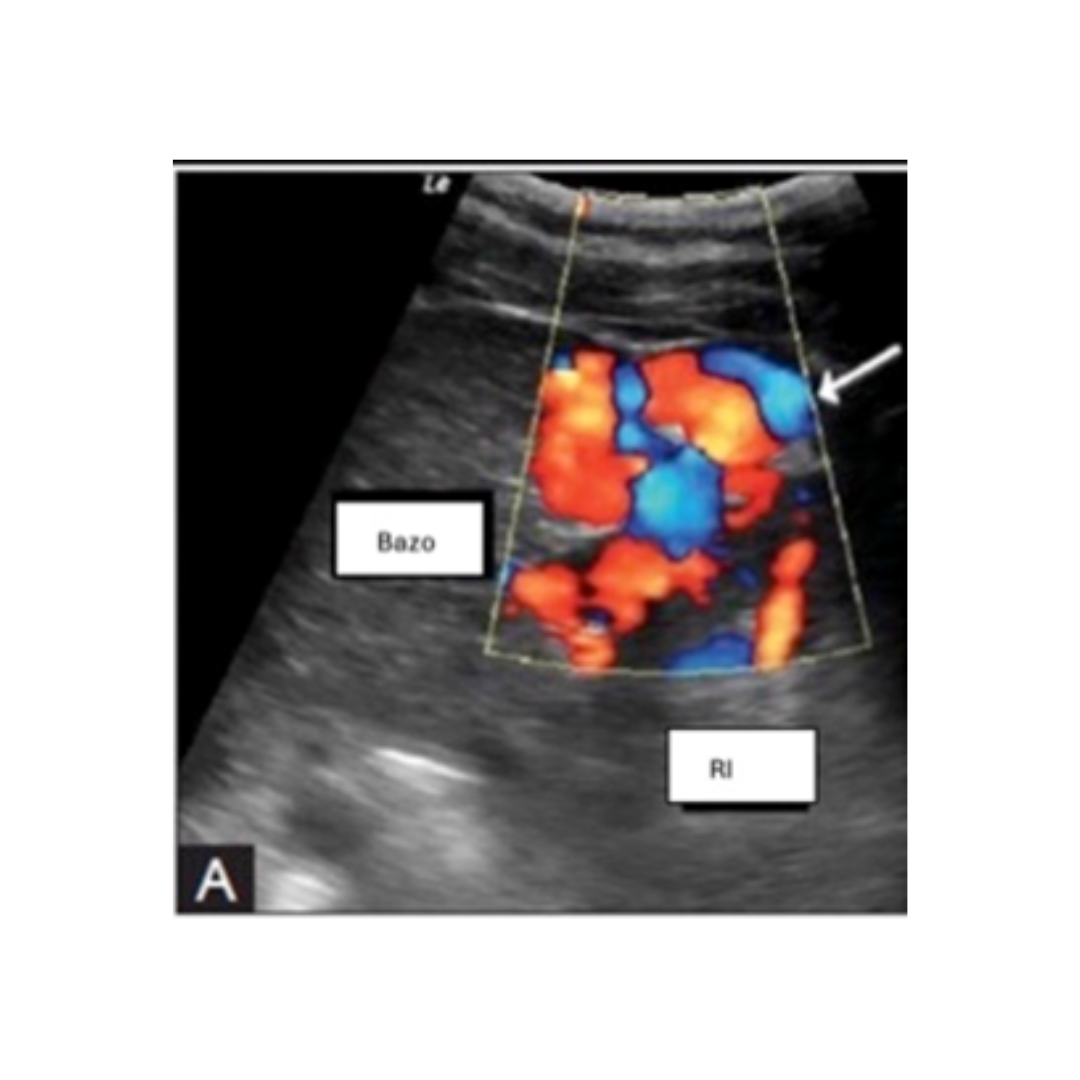

Shunt Espleno Renal

Ecográficamente se visualiza una gran cantidad de varices en hilio esplénico, sin visualización clara de la derivación.

Figura 14: Corte longitudinal ecografía con Doppler color, que demuestra la presencia de grandes y tortuosos (flecha) vasos entre el Riñón izquierdo (RI) y bazo, sugerente de shunt Espleno renal.